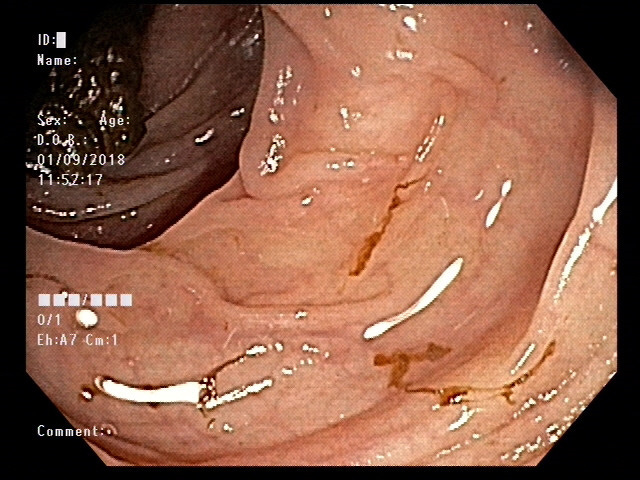

잠복혈검사에서도 WBC, RBC 모두 검출되지 않았고, 마지막으로 rectosigmoidoscopy를 시행했지만 점막에 염증이나 허혈성변화, 암과 같은 병리소견은 전혀 보이지 않고 정상이었습니다.

돌이켜보면, 환자의 심한 통증과 해당부위의 압통 때문에 S결장의 수축에 의해 정상적인 벽두께가 두껍게 평가될 수 있다는 사실을 과소평가한 것이 많은 아쉬움을 남긴 사례 같습니다. 물론, 환자의 증상이 심하고, 입원해서 여러 조치를 취했음에도 여전히 호전되지 않았기 때문에 뒤이는 여러 검사들은 초음파에서 특이소견이 없다고 언급했음에도 결국 시행될 수 밖에 없었을 것이나, 마지막에 rectosigmoidoscopy까지 해서도 아무런 병변이 보이지 않았던 것을 확인한 다음에는 못내 허탈하다는 느낌도 듭니다.